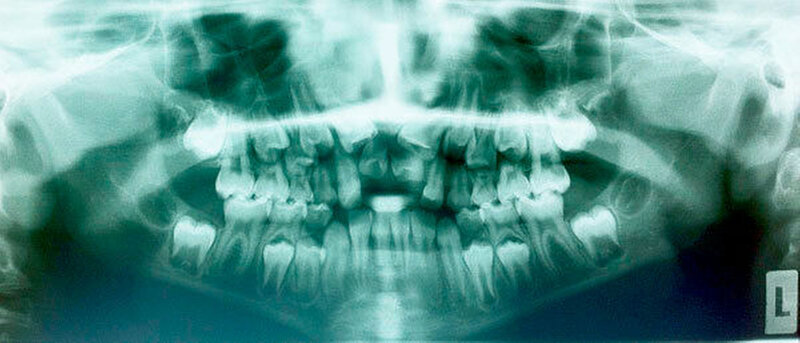

Die Prävalenz überzähliger Zähne wird im Bereich von 0,07 Prozent bis 0,6 Prozent für das Milchgebiss [Luten, 1967; Ravn, 1971; Järvinen Lehtinen, 1981; Magnússon 1984; Skrinjari Barac-Furtinovi, 1991; Yonezu et al., 1997; Chen et al., 2010] und von 0,3 Prozent bis 3,2 Prozent für die bleibenden Zähne [Luten, 1967; Bäckman Wahlin, 2001; Salcido-García et al., 2004; Leco Berrocal et al., 2007; Gündüz et al., 2008; Yagüe-García et al., 2009; Schmuckli et al., 2010; Fardi et al., 2011] angegeben. Die Mehrheit der überzähligen Zähne im Milchgebiss sind seitliche Schneidezähne im Oberkiefer, die meist mit einer normalen Morphologie und Lage durchbrechen (Abbildungen 1 bis 3) [Luten, 1967; Humerfeld et al., 1985; Garvey et al., 1999; Ferrés-Padró et al., 2009]. Der oft ungestörte Durchbruch und das Ausbleiben von Symptomen führen dazu, dass überzählige Zähne in der Milchdentition oft gar nicht diagnostiziert werden, und dies wird auch als Erklärung für die unterschiedlichen Prävalenzen überzähliger Zähne im Milch- und bleibendem Gebiss angeführt [Wang Fan, 2011]. Überzählige Zähne sind häufiger bei Männern als bei Frauen, wobei über ein Verhältnis von 1,18:1 bis 4,5:1 berichtet wird [Rajab Hamdan, 2002; Fernández Montenegro et al., 2006; Gündüz et al., 2008; Wang Fan, 2011]. In der Schweiz publizierten von Arx (1990) und Schmuckli und Mitarbeiter (2010) Geschlechterverhältnisse von 2,6:1, beziehungsweise 2,75:1. In einer aktuellen Arbeit von Mossaz und Mitarbeiter (2014) von Patienten aus dem Raum Bern lag dieses Verhältnis etwas ausgeglichener bei 1,61 zu 1.

Überzählige Zähne können einzeln oder multipel auftreten [von Arx, 1990; Rajab Hamdan, 2002; Fernández Montenegro et al., 2006; Liu et al., 2007; Gündüz et al., 2008; Ferrés-Padró et al., 2009; Hyun et al., 2009]. Einzelne überzählige Zähne treten in 65,8 bis 80,5 Prozent, doppelte in 14,5 bis 27,7 Prozent und multiple in 0,6 bis 8 Prozent der Fälle auf [Rajab Hamdan, 2002; Fernández Montenegro et al., 2006; Liu et al., 2007; Ferrés-Padró et al., 2009; Hyun et al, 2009; Mossaz et al., 2014]. Einzelne oder doppelte überzählige Zähne finden sich typischerweise in der Oberkieferfront [Rajab Hamdan, 2002; Fernández Montenegroet al., 2006; Mossaz et al., 2014]. Multiple überzählige Zähne werden vor allem im Prämolarenbereich des Unterkiefers gefunden [Abbildung 4; YUSOF 1990, Ferrés-Padróet al., 2009; Wang Fan, 2011]. Multiple überzählige Zähne sind zudem oft mit anderen Erkrankungen oder Syndromen assoziiert, dazu gehören Lippen-Kiefer-Gaumenspalten, die cleidokraniale Dysplasie oder auch das Gardner-Syndrom. Bei Patienten mit einer Lippen-Kiefer-Gaumenspalte wird vermutet, dass sich die überzähligen Zähne aus der Fragmentierung der dentalen Lamina bei der Spaltbildung ergeben [Garvey et al., 1999; Wang Fan, 2011].